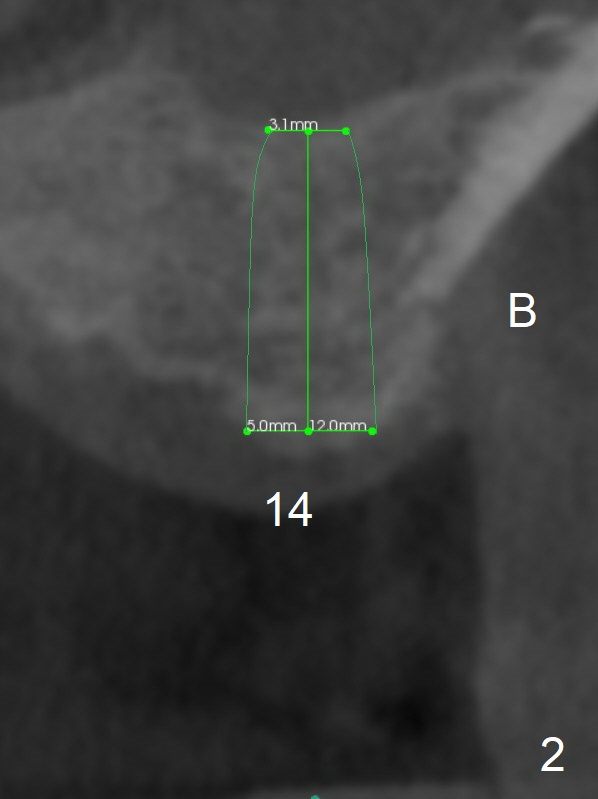

A 57-year-old man will return for #14,15 implant placement. The mesiodistal space is narrow (Fig.1: 16.8 mm vs. ~20 mm), whereas the buccopalatal dimension is wide (Fig.2,3 (B: buccal)). The diameters of the 2 implants will be determined by the former parameter. Bone density at the sites are 100-400 units. It is easy for bone expansion/condensation when bone density is 100-200 units.